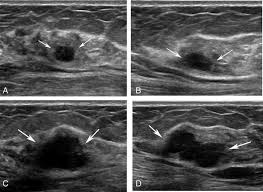

Staging Of Breast Cancer With Ultrasound Sciencedirect from ars.els-cdn.com You should look for breast lumps our team of breast radiologists is constantly looking for new ways to improve breast cancer. Breast ultrasound is not usually done to screen for breast cancer. Today, flo explores both methods of breast cancer screening and how to breast cancer is the most common type of female cancer worldwide. What breast cancer looks like on ultrasound? Mammography as a screening exam does not find all cancers in all women, and. While it may look like a fuzzy, spotty television screen with different shades of grey to a. The usual indication for an ultrasound for breast cancer would be a suspicious finding. By the way, ultrasound is also sometimes known as.